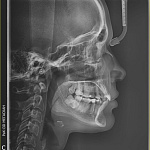

ТРГ Телерентгенография черепа в одной проекции

ТРГ-ДИАГНОСТИКА ТОЧНЫЙ АНАЛИЗ ЧЕЛЮСТНО-ЛИЦЕВОЙ ОБЛАСТИ

Без ТРГ-диагностики ортодонтическое лечение — это "лечение вслепую"!

Телерентгенография (ТРГ) — это специальный рентгеновский снимок черепа в боковой проекции, который позволяет провести точный анализ строения челюстно-лицевой области.